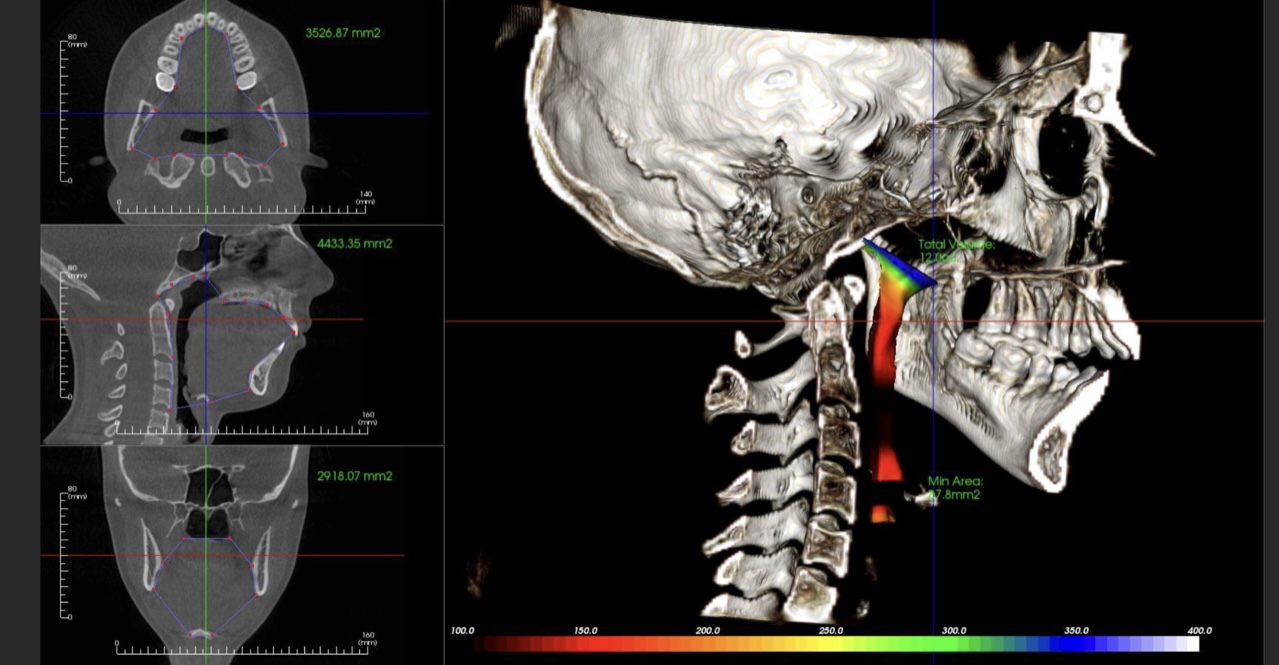

- The relationship of the compromised airway to the compromised joint and occlusion patient

- The importance of imaging and its role in your specific diagnosis and risk assessment

- How to take, order and interpret both CT/MRI images